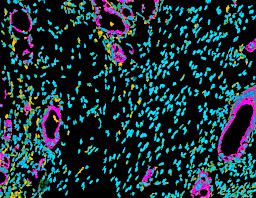

Pancreatic ductal adenocarcinoma is a lethal disease with limited treatment options and poor survival. We studied 83 spatial samples from 31 patients (11 treatment-naïve and 20 treated) using single-cell/nucleus RNA sequencing, bulk-proteogenomics, spatial transcriptomics and cellular imaging. Subpopulations of tumor cells exhibited signatures of proliferation, KRAS signaling, cell stress and epithelial-to-mesenchymal transition. Mapping mutations and copy number events distinguished tumor populations from normal and transitional cells, including acinar-to-ductal metaplasia and pancreatic intraepithelial neoplasia. Pathology-assisted deconvolution of spatial transcriptomic data identified tumor and transitional subpopulations with distinct histological features. We showed coordinated expression of TIGIT in exhausted and regulatory T cells and Nectin in tumor cells. Chemo-resistant samples contain a threefold enrichment of inflammatory cancer-associated fibroblasts that upregulate metallothioneins. Our study reveals a deeper understanding of the intricate substructure of pancreatic ductal adenocarcinoma tumors that could help improve therapy for patients with this disease.